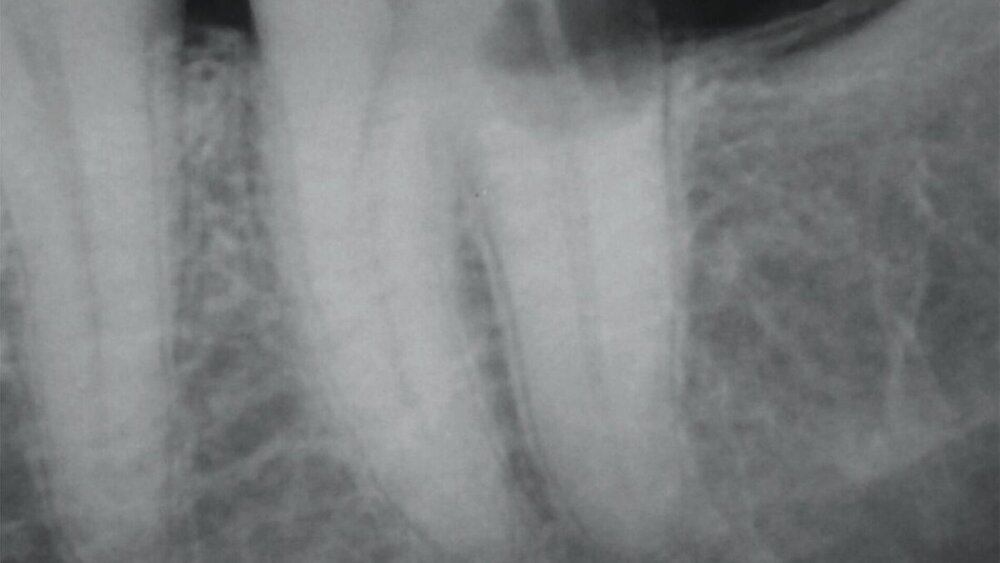

Entzündliche Resorptionen sind bei fehlender klinischer Symptomatik häufig ein radiologischer Zufallsbefund. Sie können aber auch mit einer symptomatischen Entwicklung wie irreversibler Pulpitis oder apikaler Parodontitis einhergehen. Resorptionsdefekte an der Wurzeloberfläche erscheinen im Röntgenbild aufgrund ihres raschen Fortschreitens oft zerklüftet (Abbildung 6). Entlang einer unregelmäßigen Wurzelaußenkontur sind transluzente Zonen im Sinne von „schüsselförmigen“ Resorptionslakunen unterschiedlicher Größe zu erkennen. Häufig findet man verkürzte Wurzeln mit zusätzlichen periapikalen Aufhellungen. In fortgeschrittenen Fällen kann die Resorption bis ins Zahninnere vordringen und den Wurzelkanal perforieren [Andreasen und Hjørting-Hansen, 1966; Finucane und Kinirons, 2003].